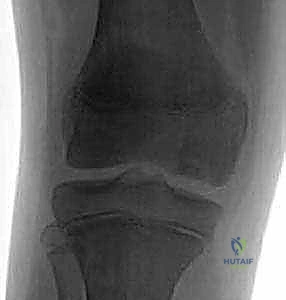

- الأشعة السينية (X-Rays): تُعد الخطوة الأولى لاستبعاد الكسور وتقييم الهيكل العظمي العام، وغالباً ما تُظهر الآفة في المراحل المتقدمة.

- التصوير بالرنين المغناطيسي (MRI): هو "المعيار الذهبي" للتشخيص. بفضل خبرة الدكتور هطيف العميقة، يتم تحليل صور الرنين لتقييم صحة الغضروف، مدى انفصال القطعة العظمية، وحالة الأربطة المحيطة. الرنين يحدد ما إذا كانت الآفة مستقرة (يمكن علاجها بدون جراحة) أو غير مستقرة (تتطلب تدخلاً جراحياً).